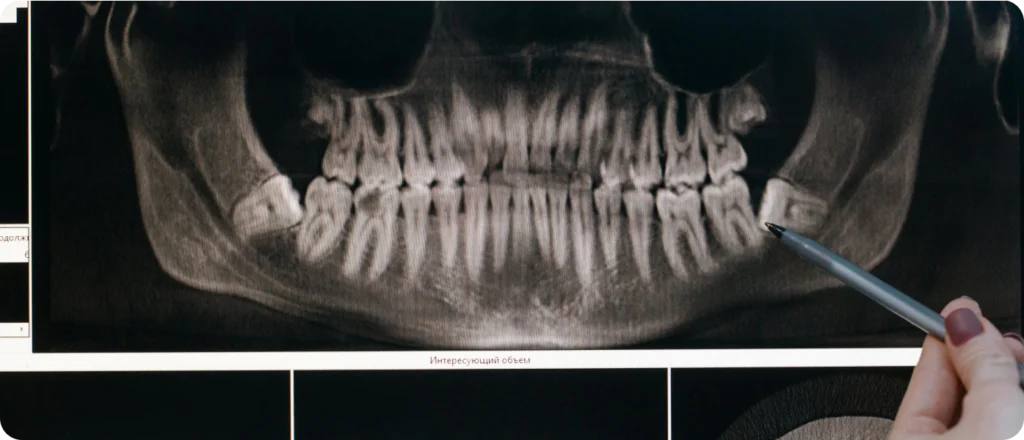

- Radiographies et photographies

Ces examens visuels et radiologiques permettent d’obtenir une vision globale et détaillée de la structure bucco-dentaire.

Ces outils permettent d’évaluer la structure osseuse, la croissance et la relation entre les mâchoires.